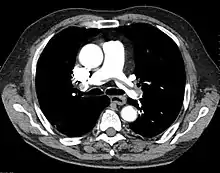

A chest X-ray can rapidly identify a pneumothorax, seen as absence of lung markings. Ultrasound can show the lack of lung sliding. However, imaging should not delay treatment.[8] CT angiography is the standard of diagnosis of pulmonary embolism. Clots appear in the vasculature as filling defects.[18]